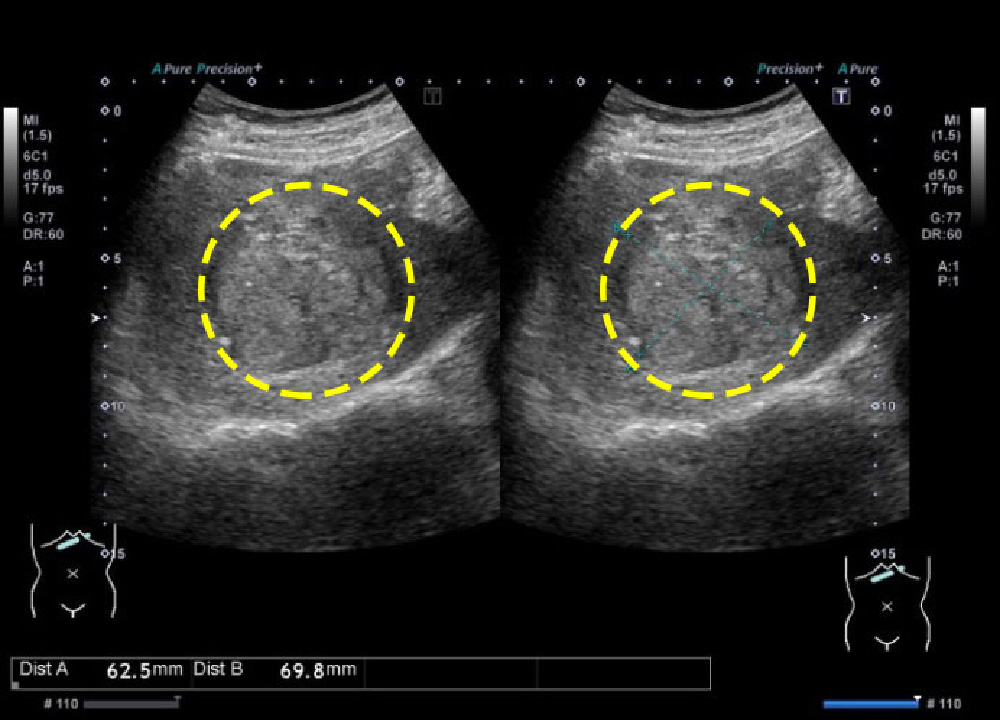

(2) 초음파검사

비침습적으로 간의 덩어리, 종양 여부를 파악할 수 있으며, 정기 검진에 자주 활용됩니다.